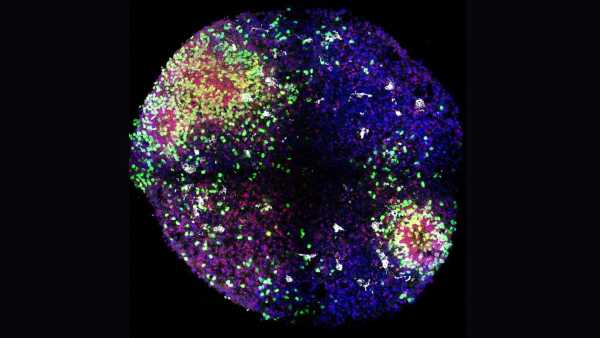

Щоб вивести більш гуманізованих мишей, дослідники спочатку вивели мишей, генетично модифікованих для ослаблення імунної системи. Коли мишам було приблизно 1-2 дні, команда ввела людські стовбурові клітини в серця тварин. Стовбурові клітини, які були вилучені та очищені з пуповинної крові, були здатні перетворитися на будь-який тип імунних клітин.

Через кілька тижнів команда ввела мишам людську версію статевого гормону естрогену. Цей гормон відомий, перш за все, своєю роллю у сприянні жіночому статевому та репродуктивному розвитку, але він також відіграє важливу роль у формуванні незрілих стовбурових клітин у зрілі, спеціалізовані імунні клітини.

Після введення людського естрогену миші почали виробляти безліч людських імунних клітин. Серед них були Т-клітини, які безпосередньо атакують мікроби, та В-клітини, що виробляють антитіла, що знищують бактерії та допомагають позначити патогени для знищення.

Щоб побачити, як гуманізовані миші реагують на вакцину, команда ввела тваринам вакцину проти COVID-19, виготовлену компанією Pfizer-BioNTech. У відповідь миші виробили людські антитіла проти коронавірусу SARS-CoV-2. Аналогічно, під час впливу білків бактерії Salmonella typhi, збудника черевного тифу, миші виробляли антитіла проти збудника.